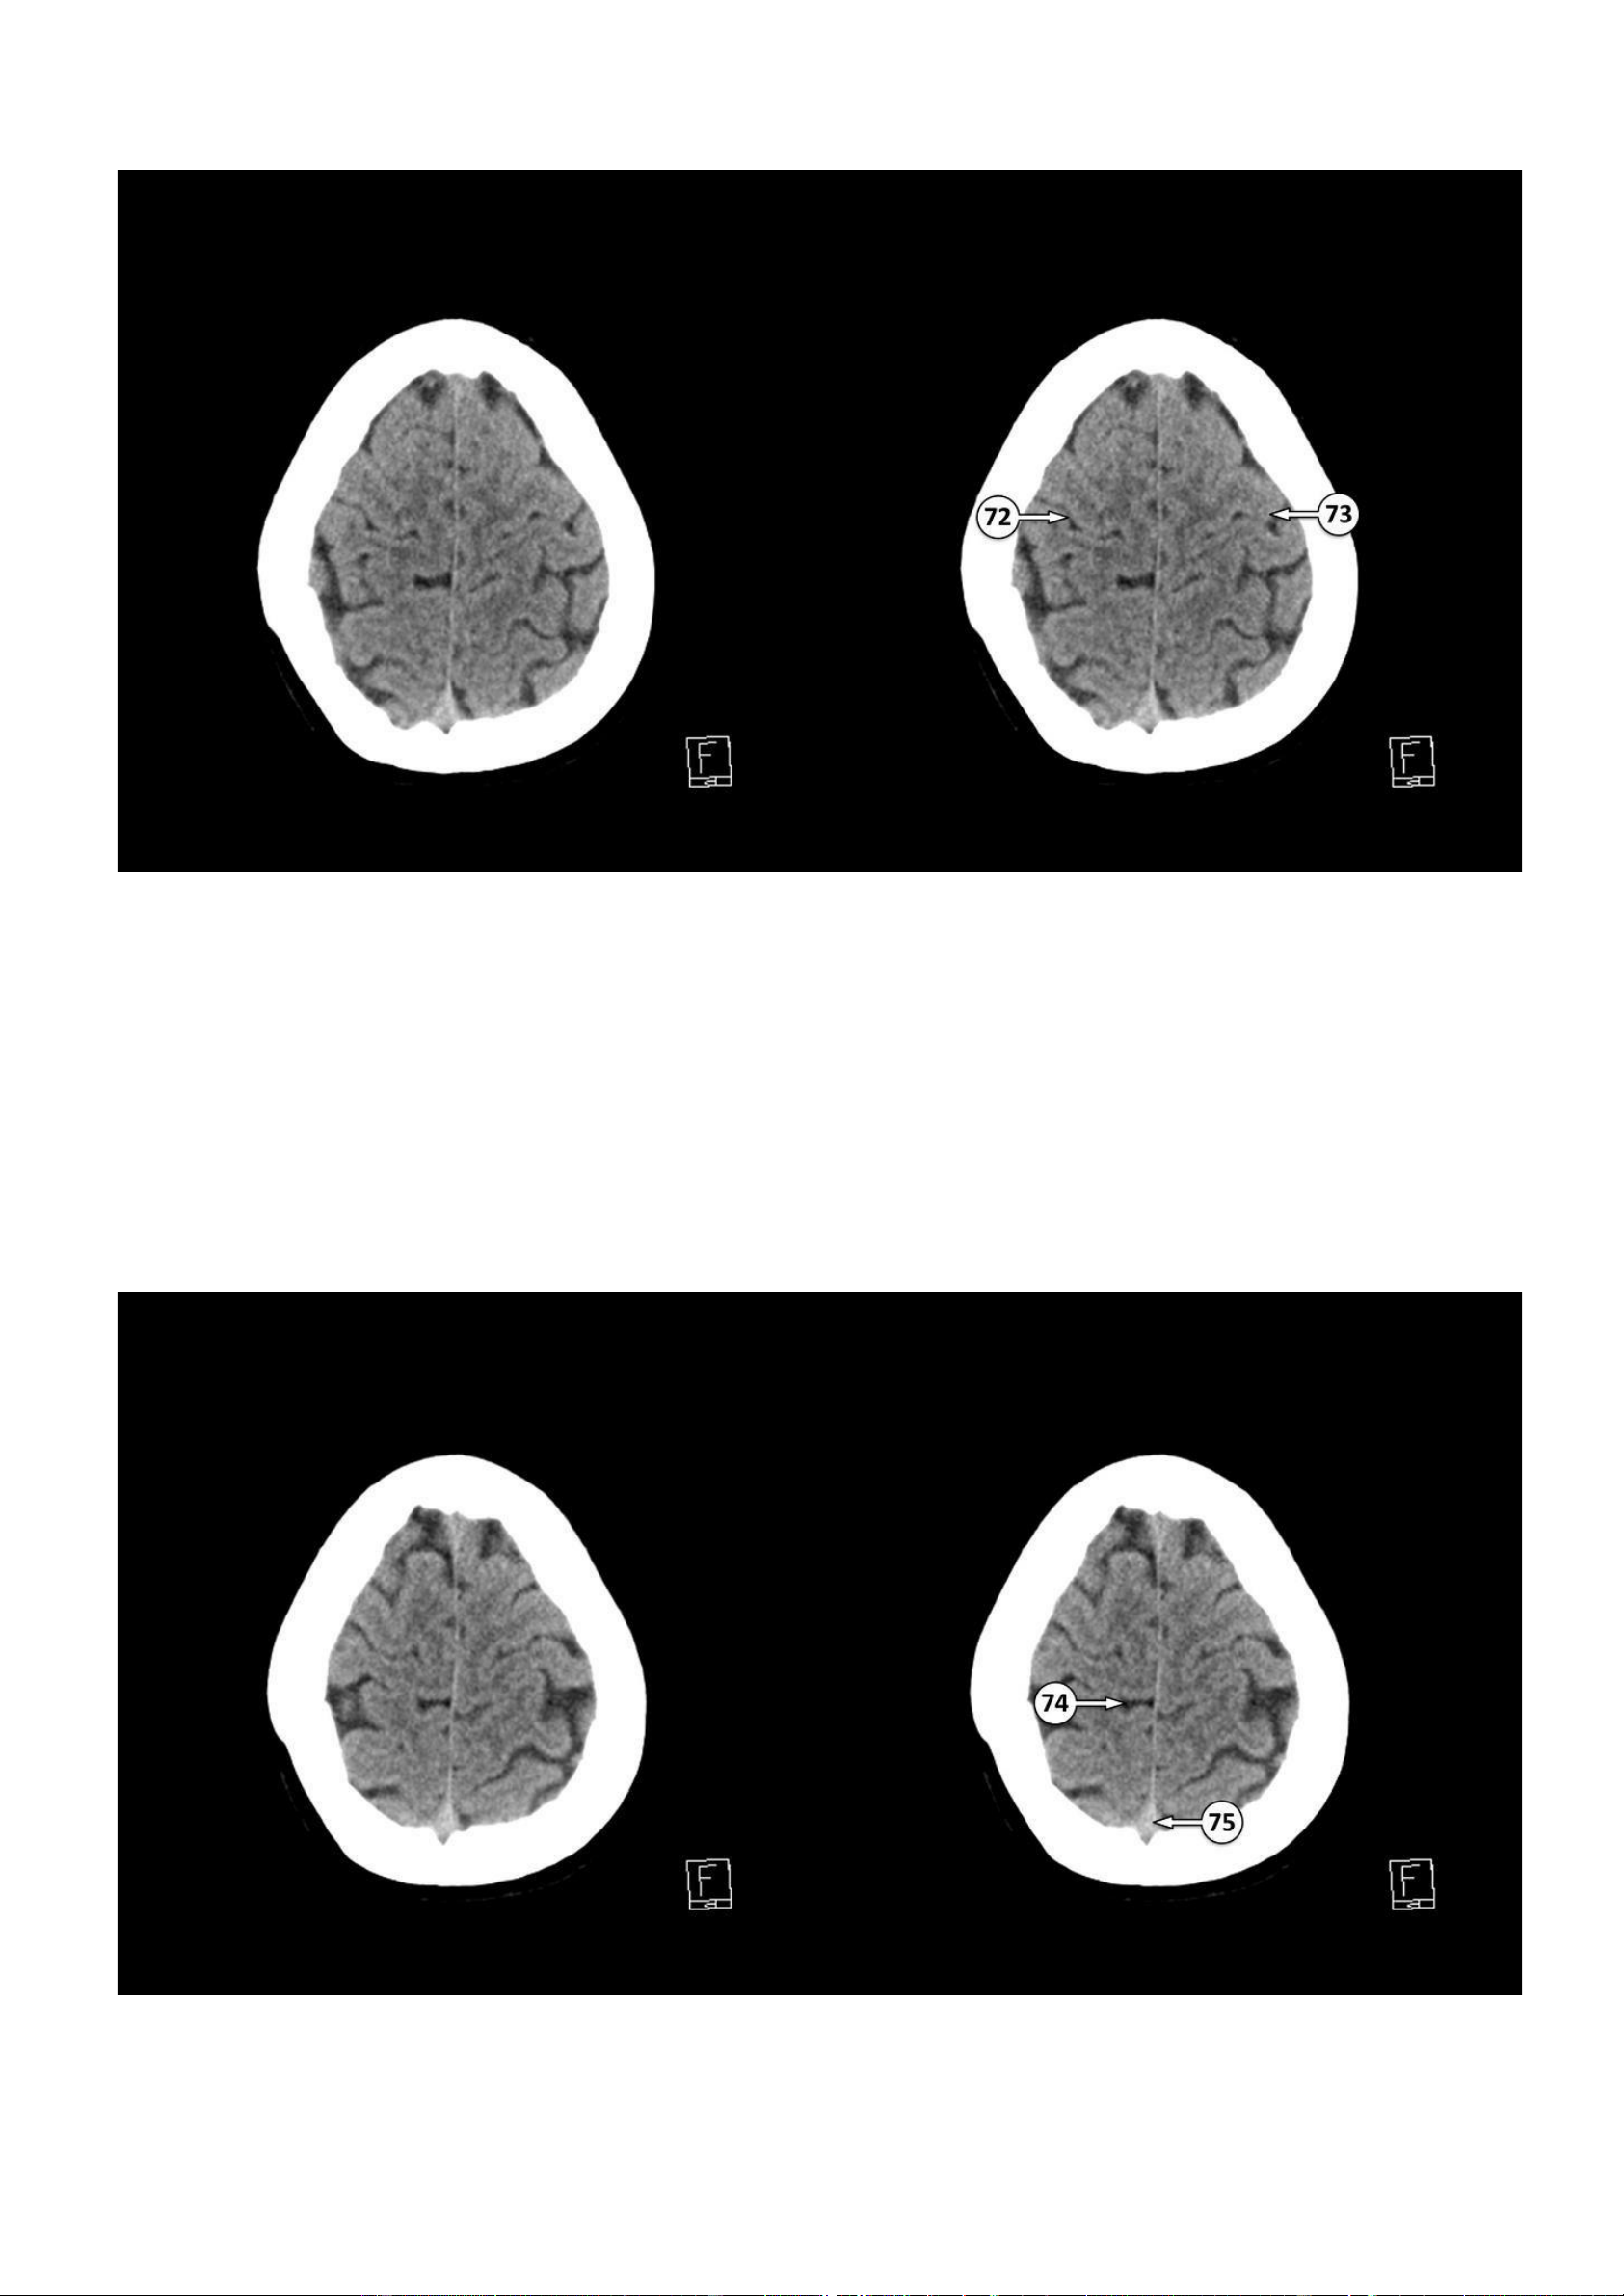

▪ Số 72: Rãnh trung tâm (rãnh Rolando)

▪ Số 73: Vỏ não vận động nguyên phát ▪ Số 74: Rãnh viền 75: Xoang dọc trên lOMoAR cPSD| 22014077